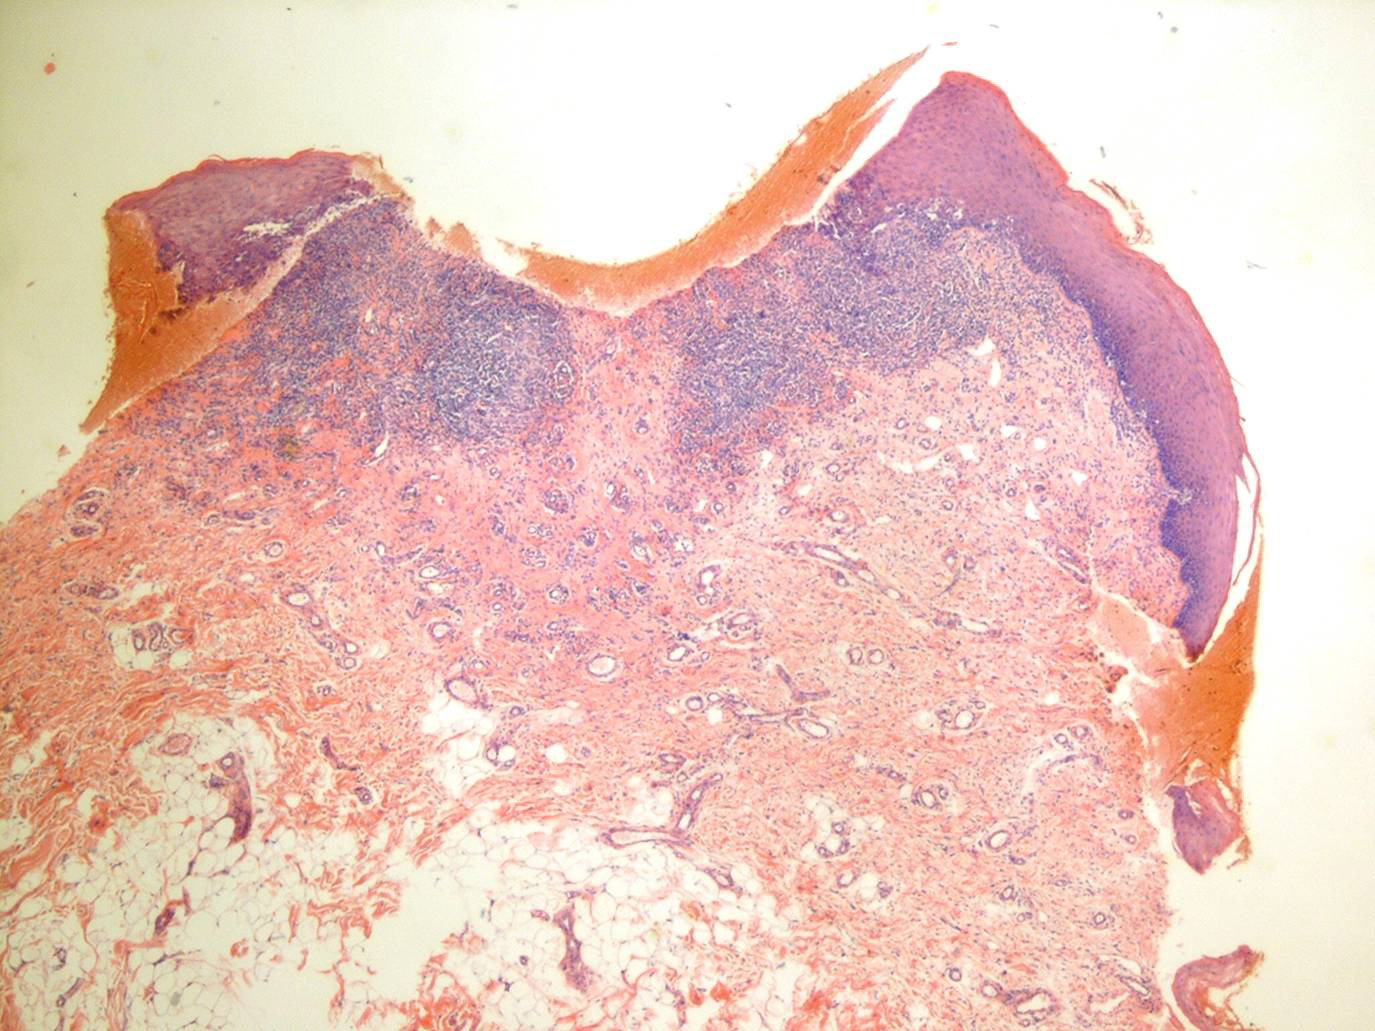

Oropharyngeal lichen planus = الحزاز المنبسط الفموي البلعومي